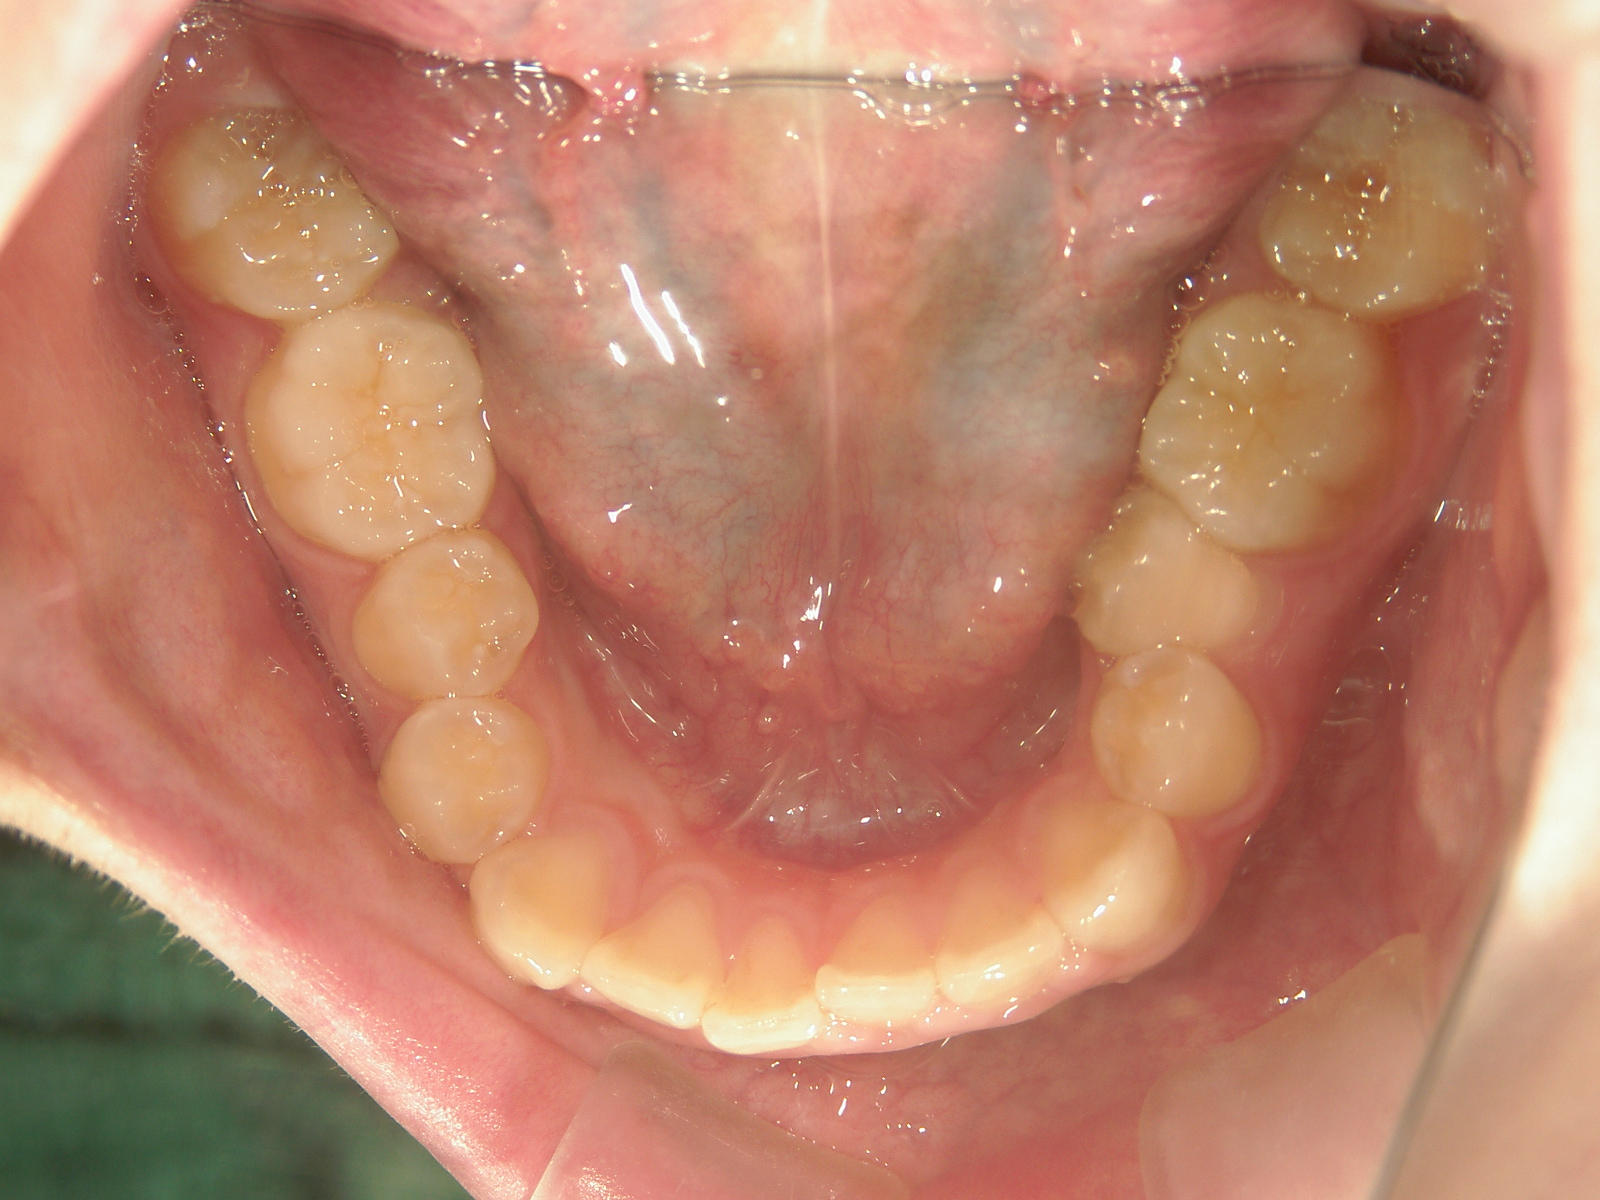

インビザライン矯正 症例(19)

主訴: 左上犬歯が出ているのが気になる